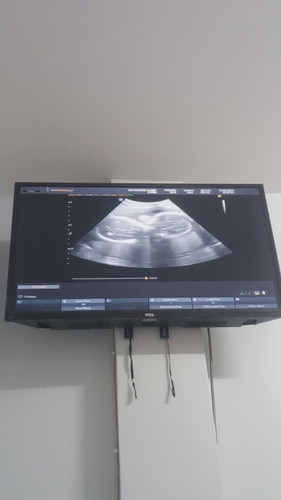

วันนี้ไปอัลตร้าซาวด์มา คุณหมอตกใจมาก555 หมอบอกได้แฝดผู้ชายค้าาา🤣 บ้านนี้ทีมมิถุนายนค่ะ แม่ๆทีมไหนกันบ้างคะ #ท้อง2